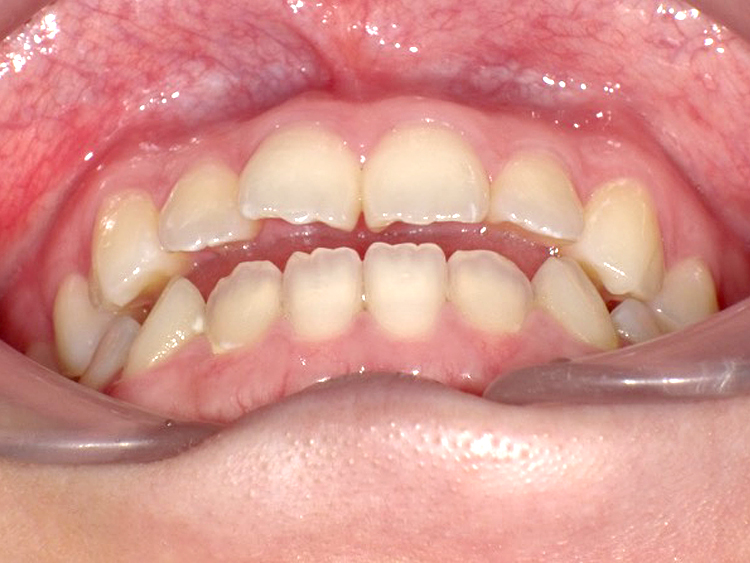

症例3

Before

After

| 主訴 | 上下の歯のガタガタを治したい |

|---|---|

| 年齢 | --- |

| 治療期間 | 約10ヶ月 |

| 治療内容 | インビザラインiGoで上下顎の治療。 狭まっていた歯並びを広げることで、 ガタガタに並んでいた歯を綺麗に並べた。 |

| 治療費 | ¥517,000(税込)+月額調整料 |

| 治療のリスク | 歯と歯の間を削ることでスペースを確保するので、 場合によっては歯が染みる症状が出ることがある。 |